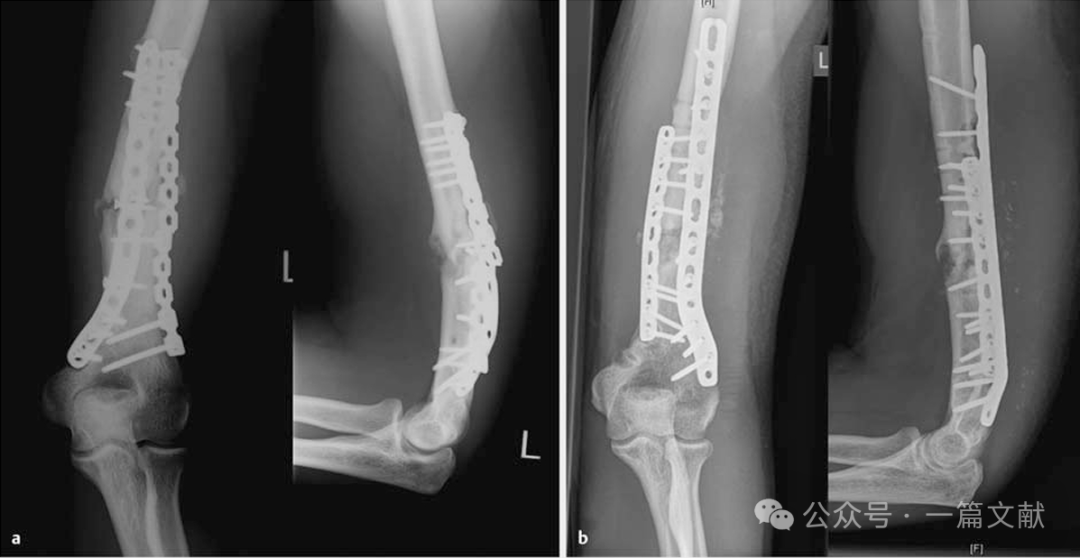

4.5 尺骨鹰嘴或尺骨近端骨折:

尺骨近端骨折可采用不同的固定方式。简单骨折可通过钢丝张力带固定或标准背侧钢板固定。两种手术的功能结果相当,但由于软组织刺激,通常需要取出植入物。

对于更复杂的尺骨近端骨折,则更倾向于采用双钢板固定。背侧结合内侧的钢板或两侧钢板放置,可用锁定钢板(LCP)。也适用于Monteggia骨折或类似Monteggia损伤的治疗,以及尺骨近端骨折不愈合的翻修病例。

如下图:55岁患者,患有类似Monteggia损伤:左图:尺骨近端粉碎性骨折,初期采用外固定架进行固定。中图和右图:桡骨头螺钉固定,以及尺骨近端双钢板固定(背侧和尺侧LCP)。

下图:26岁女性铁人三项运动员,鹰嘴骨折Mayo 2b型:左上图:术前显示鹰嘴骨折。右上图:术中首先对关节面进行复位,并使用克氏针暂时固定。下图:随后采用双钢板固定骨折。